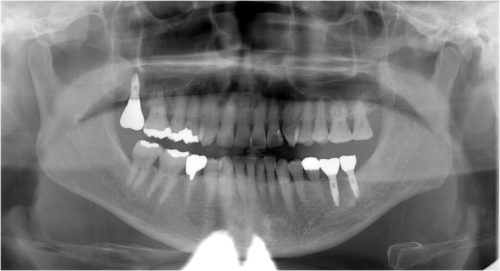

インプラント 右上4567 川口で精密インプラントなら さかえ歯科